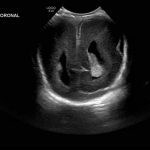

Age: 4 days (born at 24 weeks)

Sex: Male

Indication: Evaluate for germinal matrix hemorrhage

Grade 2 germinal matrix hemorrhage

Sample ReportLeft germinal matrix hemorrhage involving the caudothalamic groove and layering in the occipital horn of the left lateral ventricle without hydrocephalus (grade 2).

No abnormal brain parenchymal echogenicity or extra-axial collections.

Premature sulcation pattern.